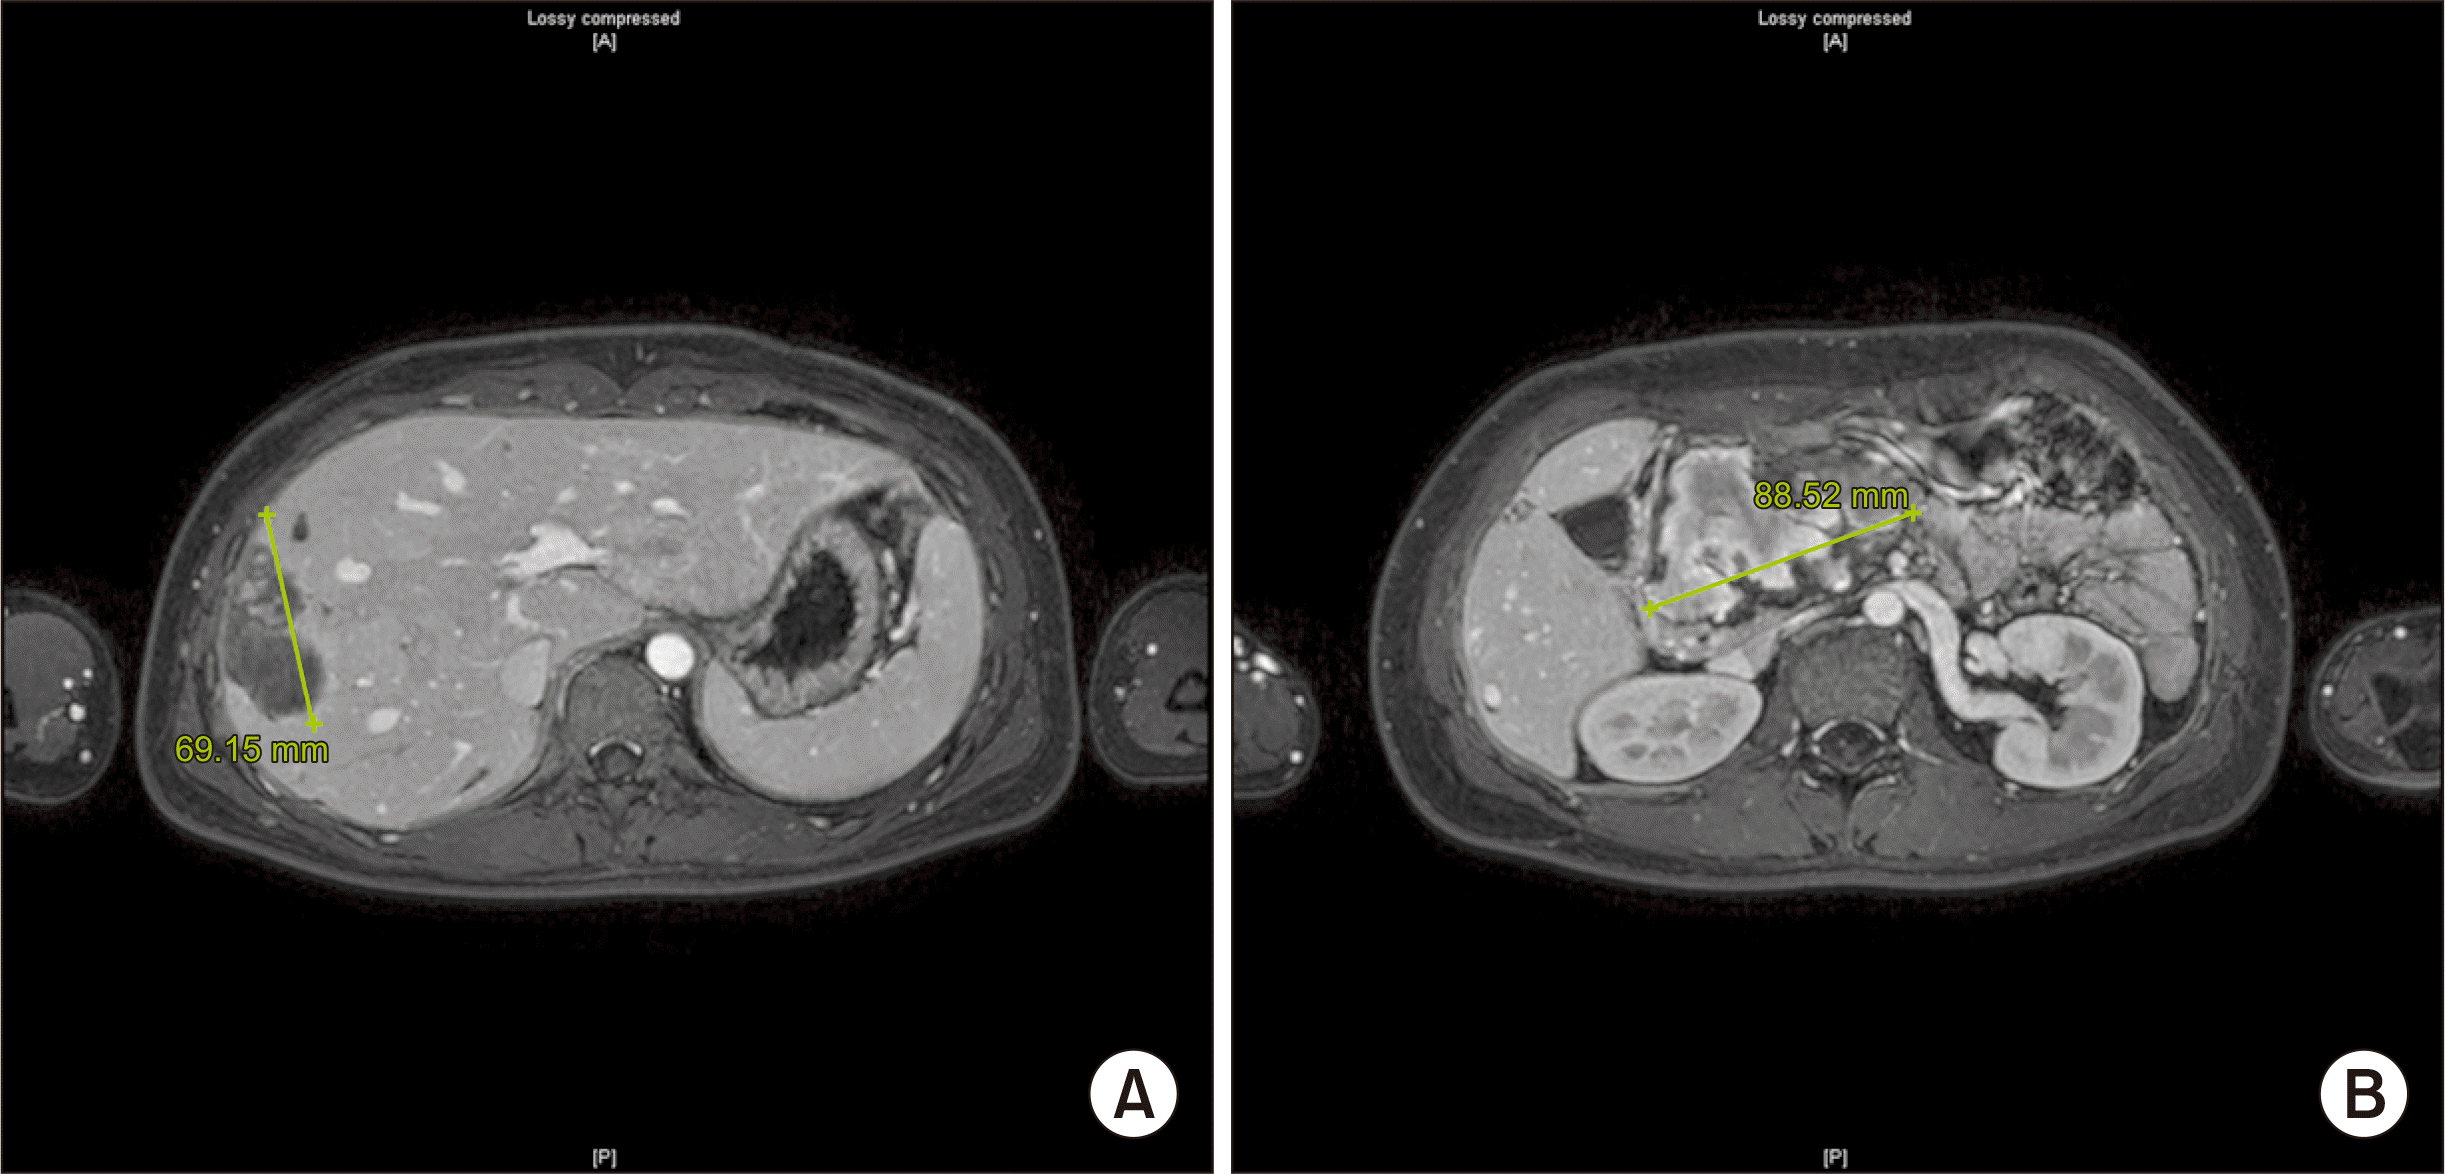

Fig. 2

Magnetic resonance imaging findings of pancreatic tumor and liver metastases. (A) Multiple metastases are observed, with sizes up to 7 cm, scattered in segment 4 (S4) and the right hepatic lobe. These metastases present with or without internal hemorrhaging. (B) A 9 cm lobulated, soft tissue-enhancing mass with significant internal hemorrhagic necrosis is seen in the head/neck portion of the pancreas.